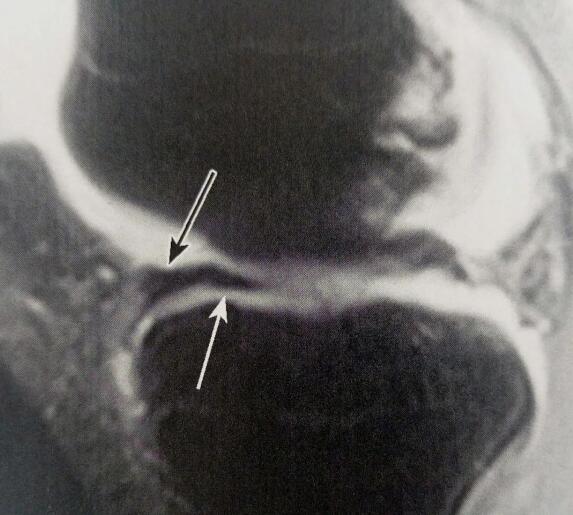

半月板前角损伤怎么治疗

半月板前角损伤可能与外伤、肥胖、姿势不当、退行性病变、骨质增生症等原因有关,患者可以通过一般治疗、物理治疗、药物治疗、手术治疗的方式改善。建议患者保持良好的心态,根据具体情况配合医生选择合适的方案治疗。

5、骨质增生症:如果患者本身存在该疾病,随着年龄的增长,关节软骨可能会逐渐破坏,失去其正常功能,从而引发半月板前角损伤。患者可以考虑在医生操作下进行关节镜手术、微创手术治疗,能够控制病情进展。